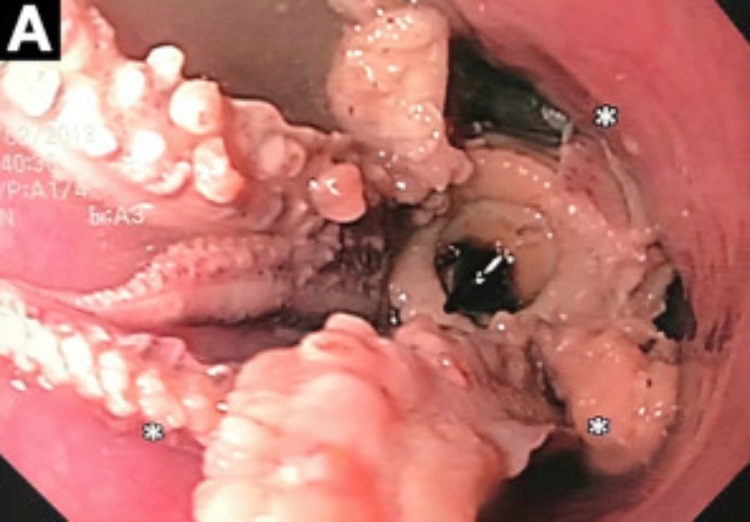

CT扫描A。图片来源:Cghjournal.org

医生们进一步调查并进行了另一项称为“食管胃十二指肠镜检查”的胃肠检查,结果令他们震惊。一只有触手的章鱼卡在了该男子的食道和胃之间,距离食道和胃的分界线仅两英寸远。